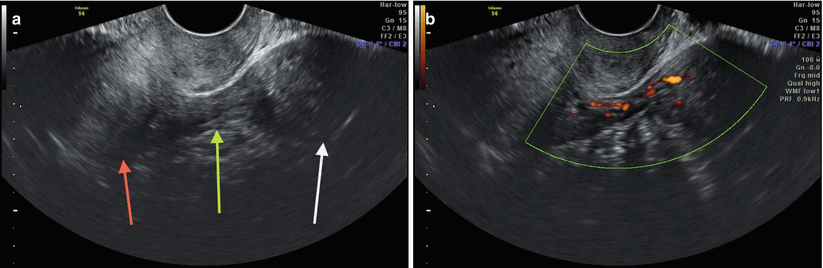

Fig. 6.2

(a) Axial ultrasound section, showing uterine body (red arrow), pedicle myoma in the left adnexal region (white arrow) and its respective pedicle (green arrow). (b) Power Doppler showing vascularization in vascular pedicle of the myoma